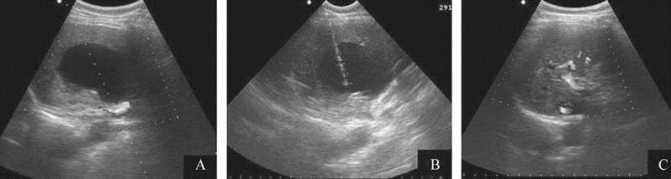

图21-36 肝囊肿经皮抽吸引流+硬化剂治疗

A.肝右叶囊肿;B.超声引导下经皮穿刺硬化治疗;C.术后半年复查囊肿完全消失